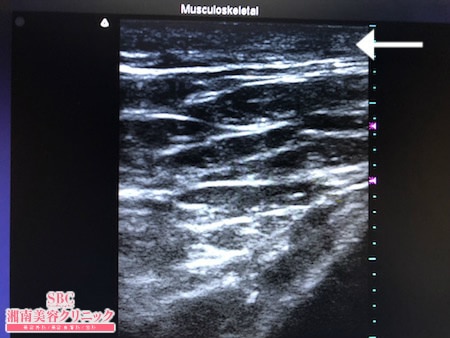

No.242768【脂肪吸引】【動画あり】湘南美容外科脂肪吸引最高責任者である竹田先生による脂肪吸引のフォトギャラリー!愛知県からご来院!他院の再手術!タバコをやめて8kg太ってしまった患者様のおなかの皮下脂肪を根こそぐ!術中3Dタッチビュー・右腰